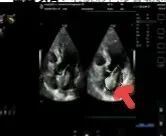

2025年深秋的一個(gè)清晨,82歲的馬奶奶(化名)因持續(xù)胸悶氣短被家人送至醫(yī)院心內(nèi)科。心臟超聲檢查顯示,她的左心房?jī)?nèi)有一個(gè)直徑近5厘米的腫瘤,隨心跳規(guī)律擺動(dòng),如同一個(gè)隨時(shí)可能破裂的“不定時(shí)炸彈”。更危急的是,冠脈造影進(jìn)一步揭示其冠狀動(dòng)脈多支血管嚴(yán)重狹窄,左前降支狹窄達(dá)95%,回旋支中段完全閉塞,右冠狀動(dòng)脈彌漫性病變—兩種致命性心臟疾病的疊加,讓這位高齡患者的生命岌岌可危。

術(shù)前冠脈造影